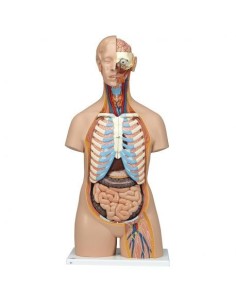

Scopri il Mondo dell’Anatomia con Modelli anatomici di Precisione

Modelli Anatomici Dettagliati per Ogni Necessità

Dal cranio in 22 parti con incastri magnetici ai modelli di colonna vertebrale, da quelli di articolazioni a quelli di cuore, ogni pezzo della nostra collezione è progettato per un’immersione totale nello studio dell’anatomia umana. I nostri modelli, realizzati tramite scansioni di ossa vere, garantiscono un’esperienza tattile autentica e una fedeltà di peso quasi identica agli originali.

Strumenti Didattici Innovativi per l’Educazione e la Pratica Medica

Essenziali per studenti e professionisti, i nostri modelli anatomici sono strumenti didattici che permettono di osservare le strutture anatomiche con precisione, eliminando la necessità di dissezioni o studi invasivi. Sono inoltre utili per spiegare ai pazienti le patologie, rendendo la comunicazione più efficace e risparmiando tempo prezioso.